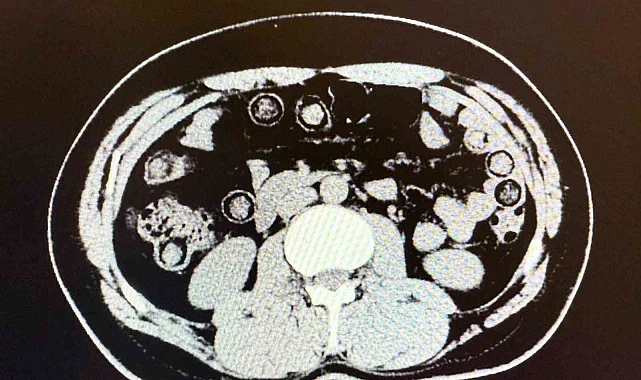

Muş Valiliği tarafından yapılan açıklamada, "Narkotik Suçlarla Mücadele Şube Müdürlüğümüzce uyuşturucu madde sevkiyatına engel olmak için yapılan çalışmalar neticesinde İran uyruklu 2 şahsın şehirlerarası yolcu otobüsü ile illere uyuşturucu madde nakli gerçekleştirebilecekleri değerlendirilmiş, 6 Aralık günü saat 11.30 sıralarında şüpheli şahısların görevlilerimizce yapılan sorgulamasında uyuşturucu madde naklettikleri yönünde kuvvetli şüphe oluşmuştur. Hastanede yapılan iç beden muayeneleri sırasında çekilen tomografi görüntülerine göre uyuşturucu madde yuttukları tespit edilmiştir. Hastanede yapılan tespit sonrasında şahısların midelerinde toplam 94 adet kapsül içerisinde daralı ağırlıkları 928 gram gelen metamfetamin maddesi ele geçirilmiştir. Şüpheli şahıslar hakkında 'uyuşturucu ve uyarıcı madde ticareti' suçundan işlem yapılmak üzere Cumhuriyet Başsavcılığına intikal ettirilmiş ve çıkarıldıkları mahkemece tutuklanmışlardır" denildi.